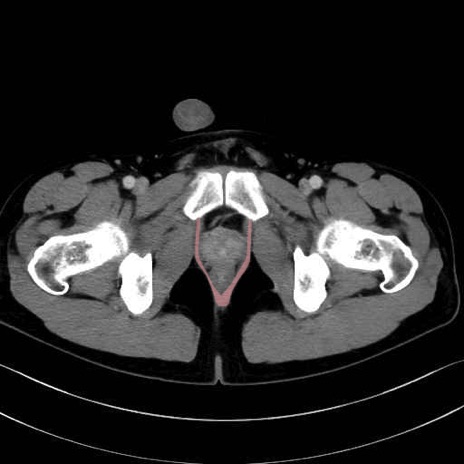

肛門挙筋(levator ani muscle)のCT画像の解剖

肛門挙筋 (Levator ani)